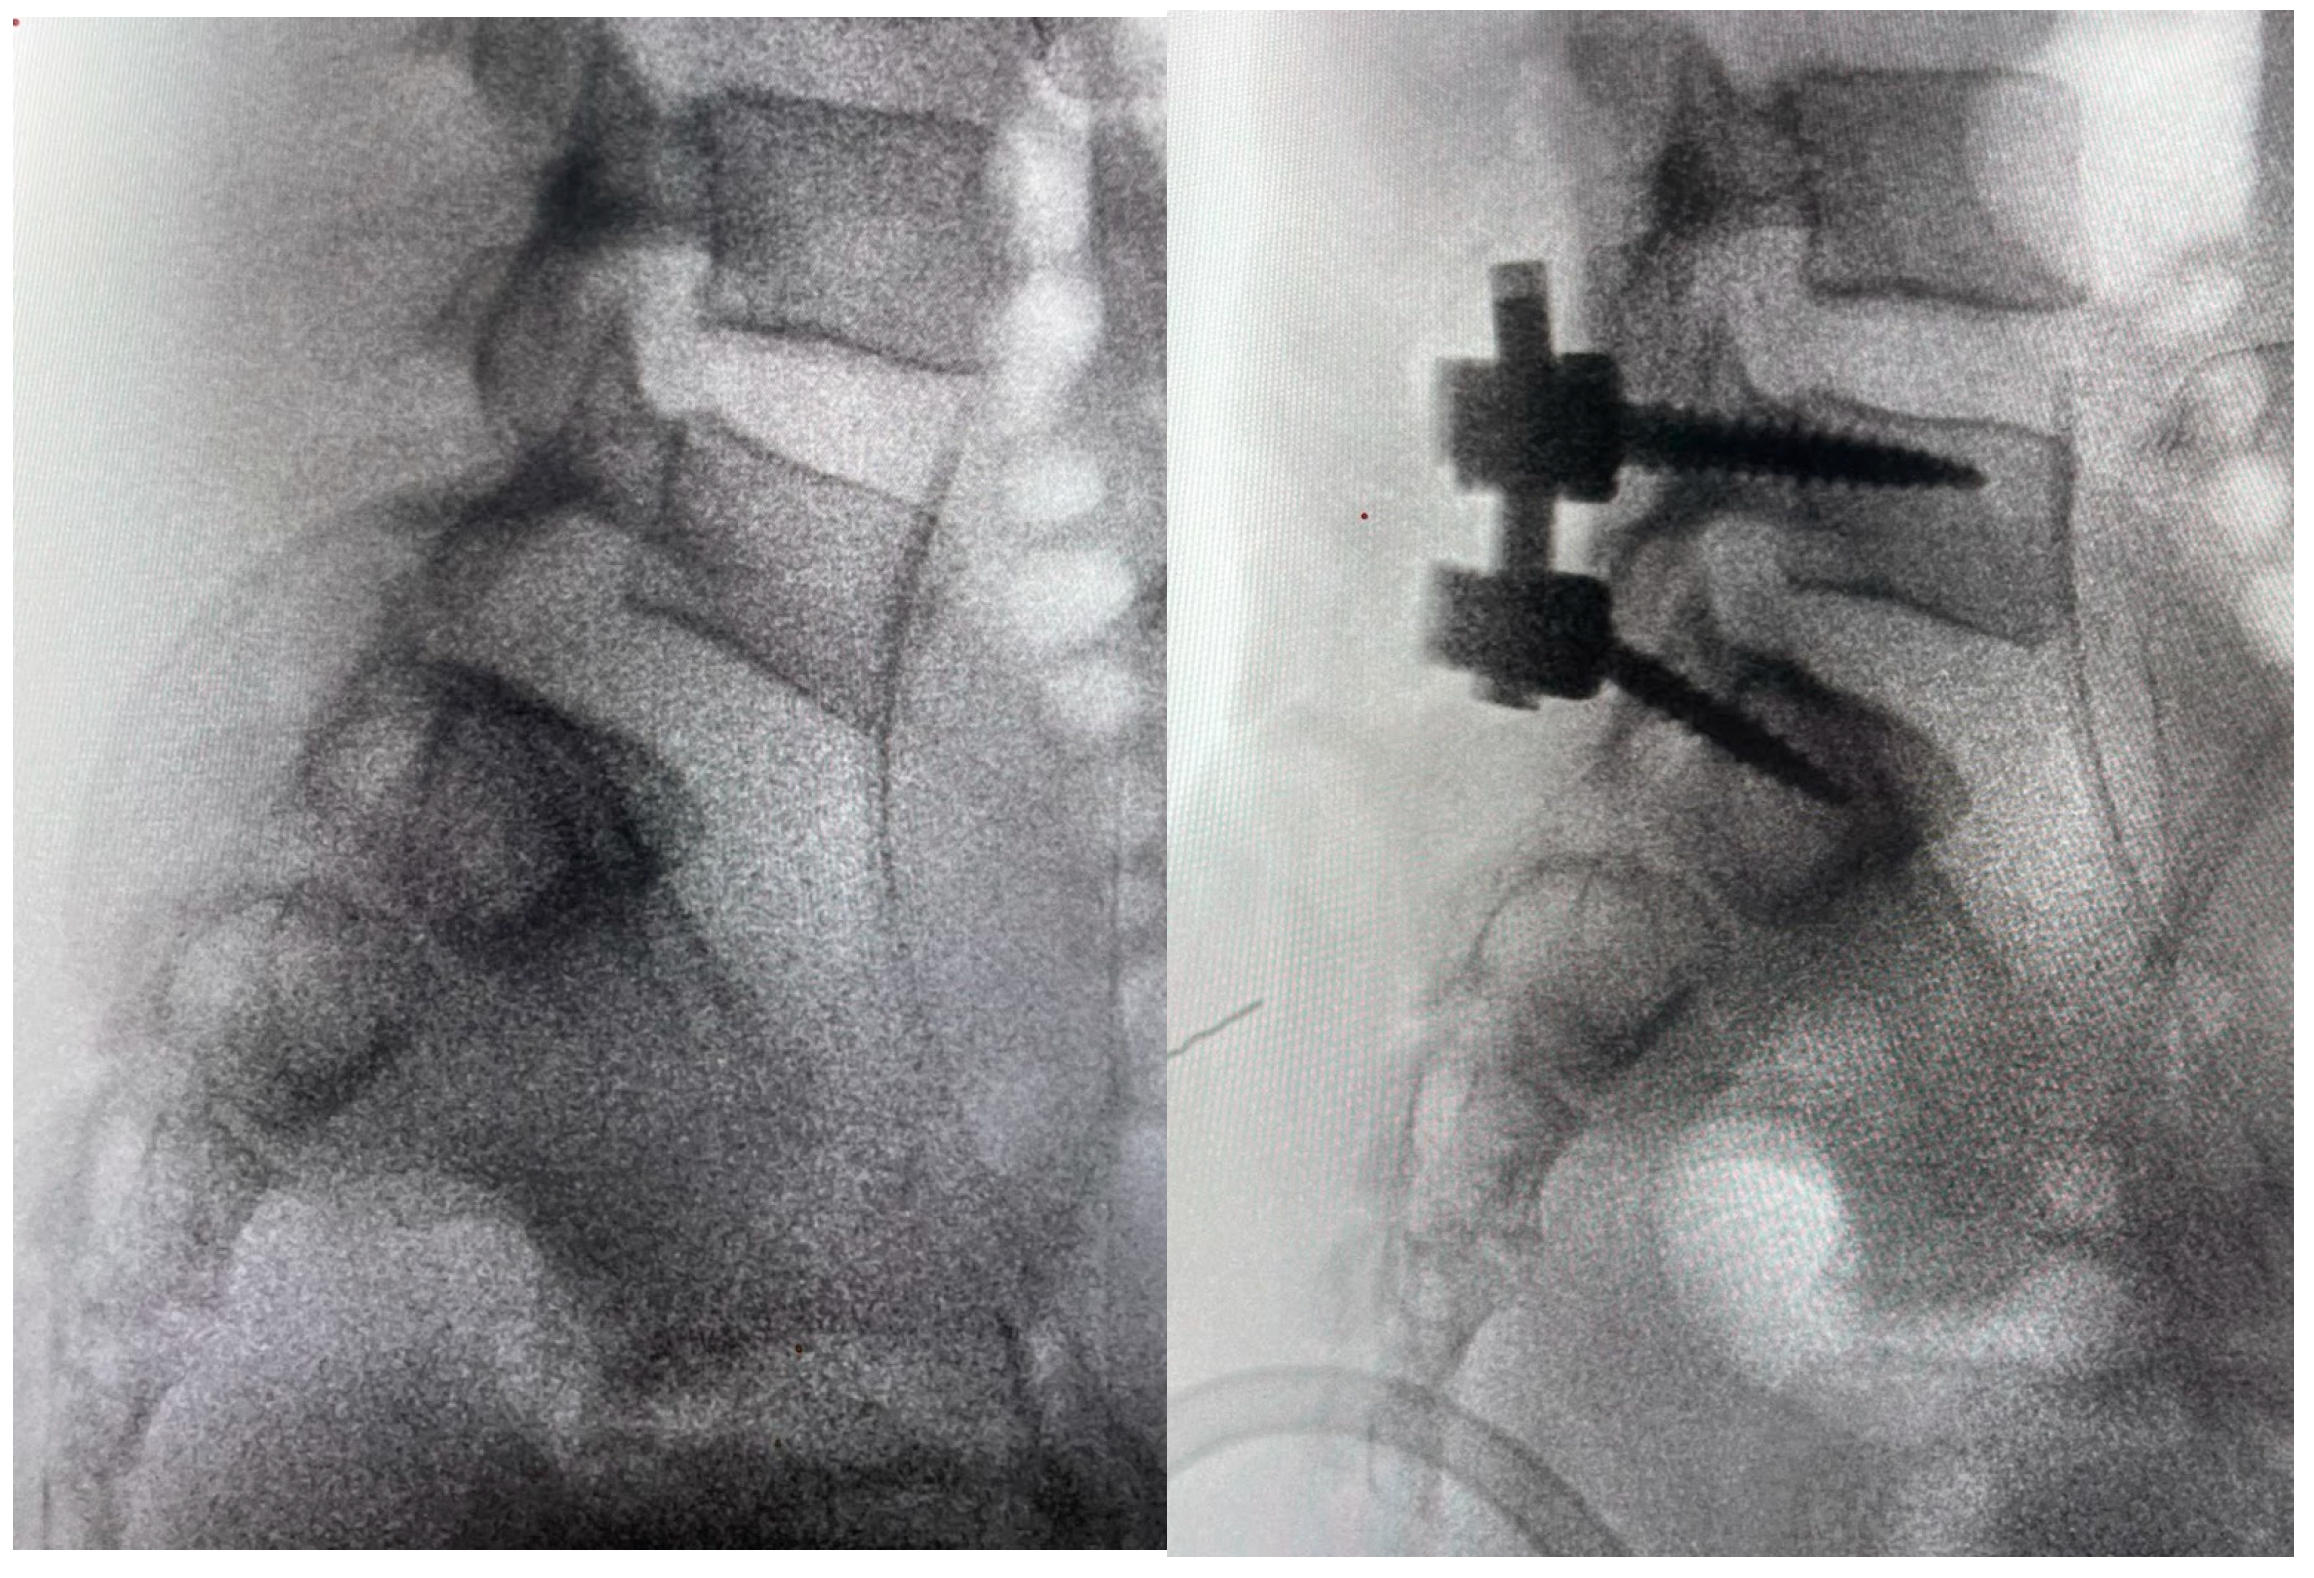

3. Case Report